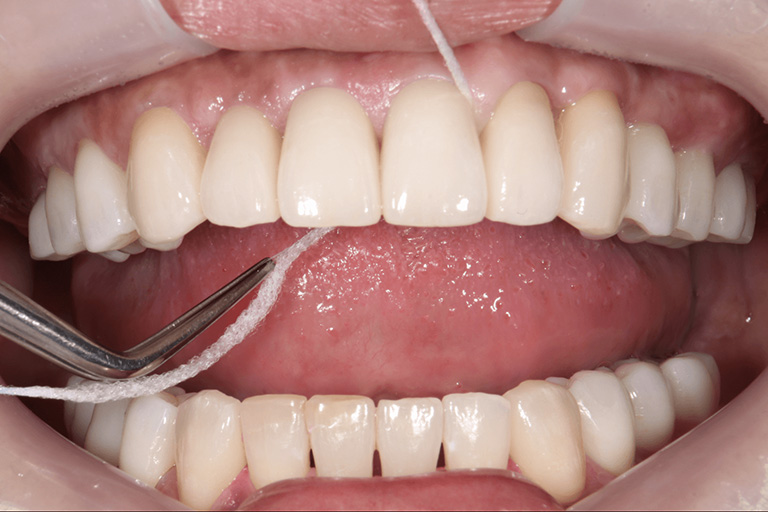

図2

この患者様の口の中には天然の歯とインプラントとセラミックの被せが入っています。3ヶ月に一度定期検診に来ていただきていますが、普段取りきれないような部分の汚れを取ることができます。